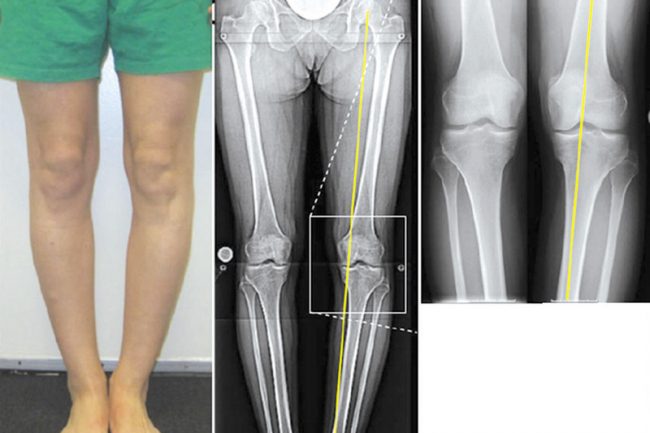

Często zgłaszają się do mnie pacjenci z bólem stawu po przeciążeniu, ale bez urazu. Wielkie zdziwienie napotyka moich pacjentów, gdy padają słowa „choroba zwyrodnieniowa”. Pojawiają się myśli: „Jak to, ja? W moim wieku?”